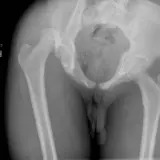

Over 2,100 interactive radiology cases, curated by radiologists for your level of training. Scroll, window, and view cases full screen — just like on PACS. Click linked findings in each writeup to jump straight to them on the image. Cases include sample reports, a focused discussion section, original illustrations, and videos.

Casos totalmente interactivos con las herramientas que esperaría de un PACS: scroll, ventana, zoom, pan, mediciones, ROI y modo de pantalla completa.

• Anotaciones enlazadas

Anotaciones extensas resaltan los hallazgos clave directamente sobre los casos. Haga clic en los hallazgos enlazados dentro de la descripción del caso para saltar a su ubicación exacta en el estudio.